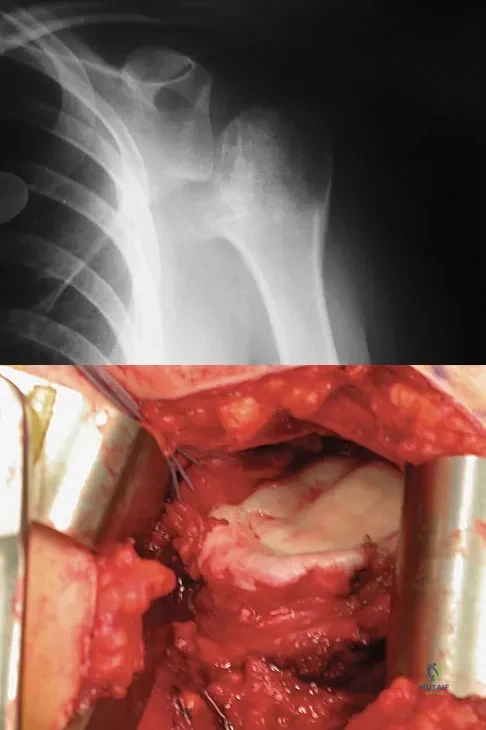

Figures 4a and 4b show the radiographs of a 53-year-old woman who was injured in a fall. After initial closed reduction, what is the preferred treatment for this fracture?

Explanation

This elbow fracture-dislocation involves a radial head fracture, coronoid fracture, and ulnohumeral dislocation (terrible triad). Several algorithms exist for treatment; surgical treatment is indicated. The treatment should address the radial head. Studies have shown replacement to be superior to repair in comminuted fractures. The coronoid may be addressed in unstable cases at the time of radial head excision and replacement. Lateral ligamentous repair is carried out during closure of the lateral elbow capsule. Medial ligamentous repair also may be undertaken but usually in concert with bony repair. Hinged external fixation remains an option when instability exists following bony and soft-tissue repair. Acute ulnar nerve transposition is rarely indicated. Ring D, Jupiter JB, Zilberfarb J: Posterior dislocation of the elbow with fractures of the radial head and coronoid. J Bone Joint Surg Am 2002;84:547-551.

References:

- Pugh DM, Wild LM, Schemitsch EH, et al: Standard surgical protocol to treat elbow dislocations with radial head and coronoid fractures. J Bone Joint Surg Am 2004;86:1122-1130.

A 28-year-old man sustained a shoulder dislocation 2 years ago. It remained dislocated for 3 weeks and required an open reduction. He now reports constant pain and has only 60 degrees of forward elevation and 10 degrees of external rotation. He desires to return to some sporting activities. An AP radiograph and intraoperative photograph (a view of the humeral head through a deltopectoral approach) are shown in Figures 31a and 31b. What is the best treatment option to decrease pain and improve function?

Explanation

The radiograph and intraoperative photograph show osteonecrosis with near complete head loss/collapse. A stemmed implant is more appropriate in this patient because there is very little bone to support a resurfacing implant. In a younger patient, a glenoid implant should be delayed as long as possible because of the eventual need for revision secondary to glenoid loosening and wear, especially in a young active male. The hemiarthroplasty may be converted to a total shoulder arthroplasty in the future. Levy O, Copeland SA: Cementless surface replacement arthroplasty of the shoulder: 5- to 10-year results with the Copeland mark-2 prosthesis. J Bone Joint Surg Br 2001;83:213-221.

References:

- Burroughs PL, Gearen PF, Petty WR, et al: Shoulder arthroplasty in the young patient. J Arthroplasty 2003;18:792-798.